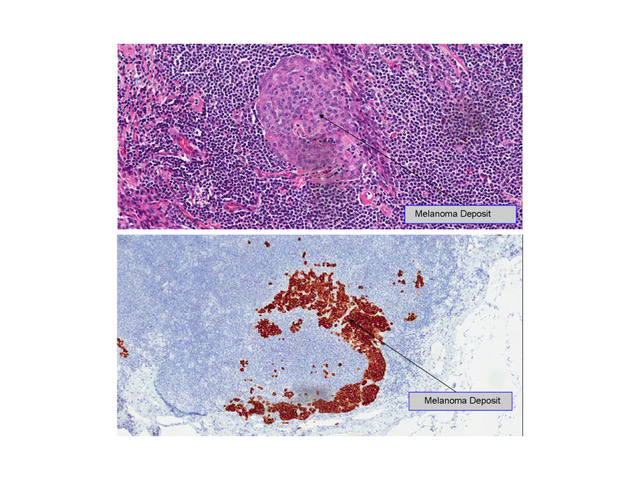

Pathology for skin cancer, particularly melanoma can be difficult for pathologists to interpret. The current UK guidelines mandates that all melanomas are reported independently by two separate pathologists, one of whom must have specific qualifications in reading skin cancer slides (dermatopathologist). To ensure the highest standards through his service, Mr Peach only sends the lesions and lymph nodes he has removed to dermatopathologists who he regularly interacts with as part of his private and NHS practice.